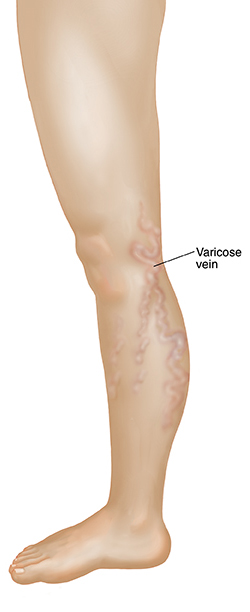

Varicose veins are enlarged veins that twist and bulge. You can see these cord-like veins just under the skin. Spider veins, are damaged blood vessels just under the skin that look red, blue or purple.

Do you often hide your legs because of the way they look? You may have noticed tiny red or blue bursts (spider veins). Or maybe you have veins that bulge or look twisted (varicose veins). If so, there are treatments that can help.